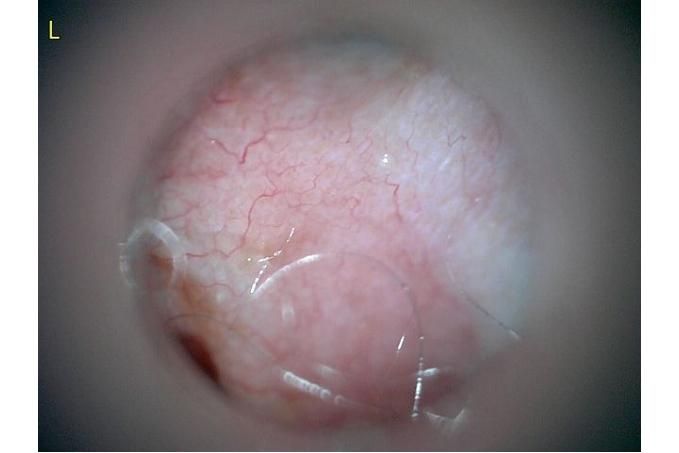

오늘 낮과 방금 5분전에 일어난 일인데요.. 강아지 귀질환 중에.. 옷입히고나서 귀를 바닥에 대고 비비거나, 귀에 통증을 호소하면서 잠깐 비틀비틀 걷는 경우 이런 경우 대체 뭘까요? 외이염일때도 이럴수도 있을까요? 아니면 중이염 내이염일지.. 한 2~3분정도 통증을 호소하다 지금은 또 정상이 됬는데 옷입을때만 옷의 목카라 부분이 귀에 닿을때 문제가 되는 느낌입니다. 평상시엔 가끔 양쪽 귀를 긁거나 귀를 자주 터는 정도입니다. 특이사항은 오른쪽귀 솜 돌돌 말아 귀안에 넣어줘도 비명을 지르며 엄청 아파하는데(작년11월경) 왼쪽은 안아파합니다)

그리고 용종이라고 코멘트 달아주셔서 저 검이경 사진 찍은곳에 물어보니 용종은 아니라고합니다.

저 부분 용종 아니라합니다

제가 가장 알고싶은점은. 저렇게 옷깃에 귀가 시쳐도 아파할정도면 이게 외이염일까요 중이염일까요 내이염일까요? 얼마나 아픈지 옷한번 얇은 내복 평상시 입던거 입히면 입히고 나서 바로 온집을 돌아다니면서 바닥에 귀를 대고 정신나간애처럼 비비고 비틀비틀 걷습니다 그러다가 2~3분후 다시 정상으로 돌아옵니다

(근데 또 귀를 조물락 조물락 만져도 안아파합니다, 다만 솜을 길게 해서 넣으면 솜만 넣어도 아파합니다 특히 오른쪽요 왼쪽은 안아파합니다)